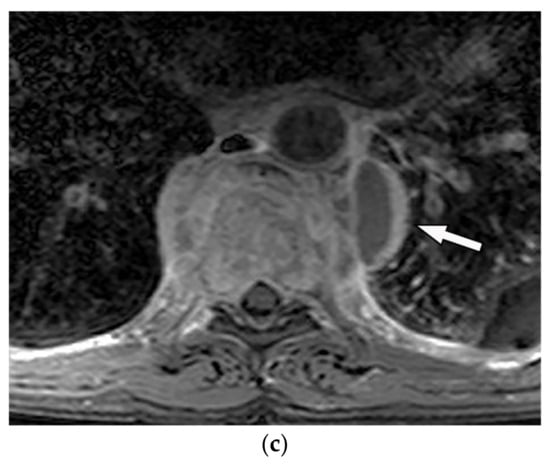

Cortical expansion with lobulated border, abundant peripheral sclerosis, and rarely internal calcification are the main radiologic appearances of chondromyxoid fibroma on radiograph and CT [3,33]. Cortical expansion with lobulated border, abundant peripheral sclerosis, and rarely internal calcification are the main radiologic appearances of chondromyxoid fibroma on radiograph and CT [3,33]. On MRI, varying degrees of signal intensity can be identified. Isointensity on T1-weighted and intermediate to high intensity on T2-weighted images have been reported. Peripheral hypointense rim seen on both T1-weighted and T2-weighted images reflects the sclerotic rim. The absence of diffusion restriction and diffuse moderate to intense contrast enhancement is noticeable (Figure 10) [3,33]. The absence of diffusion restriction and diffuse moderate to intense contrast enhancement is noticeable (Figure 10) [3,33].

Figure 10.

A 26-year-old man with right chest pain. The axial contrast-enhanced CT in soft tissue (a) and bone window (b) demonstrate well-defined oval eccentric lytic bone lesion within the posteromedial aspect of the chest wall on the right side (arrow) without intracanal extension or periosteal reaction; adjacent focal vertebral body scalloping is also shown. (c,d) Axial T1W and T2W show low signal intensity in T1W and intermediate to high intensity in T2W with the peripheral hypointense rim due to the sclerotic rim (arrow).